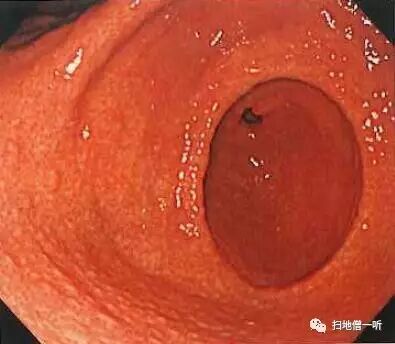

萎缩线的肛侧粘膜可见多发弥漫性小隆起,称为鸟肌样胃炎(鸡皮样胃炎、结节样胃炎),其为HP感染后淋巴滤泡反应性增生所致。报道称年轻人的鸟肌胃炎常有未分化癌的高发。

鸟肌胃炎